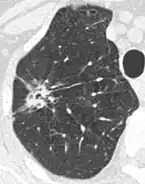

- Pleural retraction is far more common in cancers.[9] It is the pulling of visceral pleura towards the nodule.[9]

Nodule with pleural retraction.[9] -

In this case, pleural retraction is seen as a triangular fat component.[9]